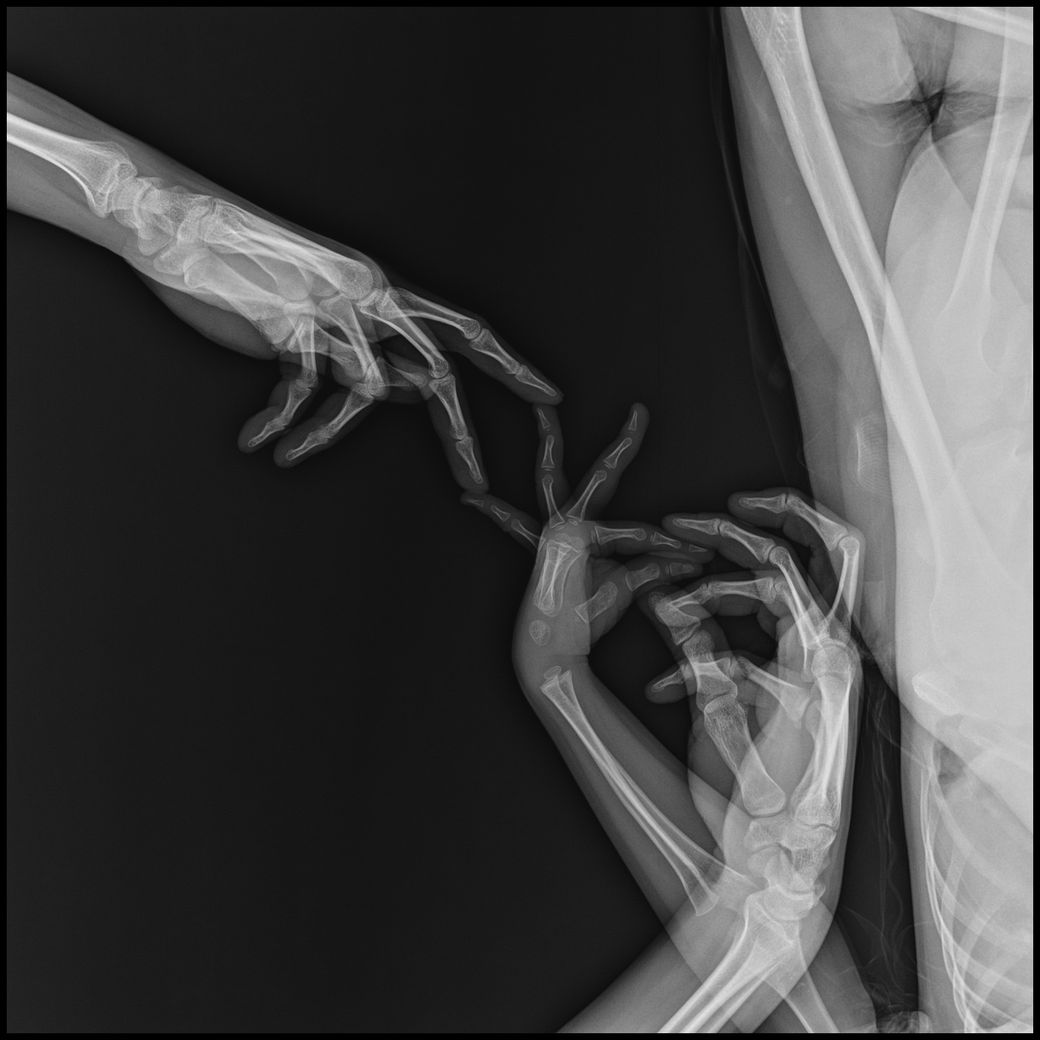

• 4번 째 사진

아기 손발 엑스레이를 찍게되었는데요.

고관절,복부일부,생식기등 민감부위등이 추가로 촬영되었고